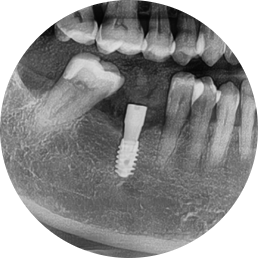

수술 직 후 엑스레이 사진

✅ #46 임플란트 단독 식립

✅ 잇몸뼈 상태 양호 → 뼈이식 없이 바로 수술 가능

✅ 서울오브치과의 디지털 가이드 시스템 적용 → 해부학적 구조를 고려한 안전한 수술 경로 확보